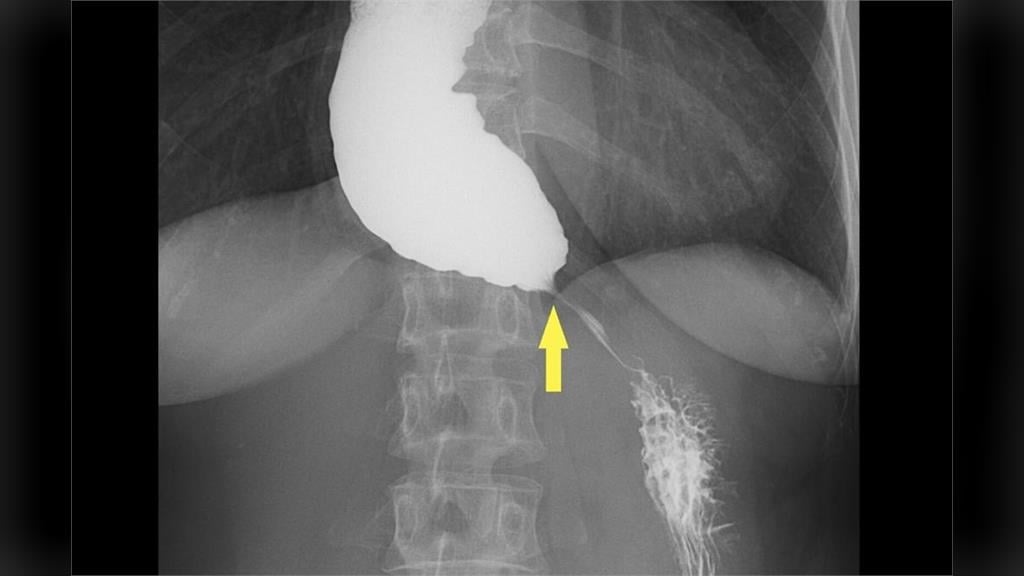

台北慈濟醫院胃腸肝膽科醫師詹崴宇指出,婦人首先接受食道攝影與食道高解析度壓力檢測(HRM),其中食道攝影顯示食道末端出現典型「鳥嘴狀」狹窄,但壓力檢測結果卻沒有典型下食道括約肌壓力上升表現,讓診斷一度陷入兩難,所幸,接著以新式診斷工具功能性管腔成像探頭檢查,終於確診。

照片來源:台北慈濟醫院提供